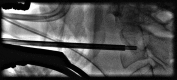

Pathologic fractures involving the C2 vertebral body and odontoid process pose a unique dilemma, as the surgical approach for direct odontoid process screw fixation has several limitations. There have been a small number of transoral approach C2 vertebroplasty or kyphoplasty reported in the literature. Previous attempts were performed utilizing fluoroscopy or CT guidance. We report a case of a fluoroscopically guided transor-al approach vertebroplasty in a patient with a lytic lesion involving the C2 vertebral body, extending into the odontoid process with an underlying pathologic fracture. This case is unique as two separate punctures were required in order to adequately stabilize the pathologic fracture, CTA was performed preoperatively to better evaluate regional vasculature, and a post-procedure rotational flat panel CT was performed to assess cement placement.